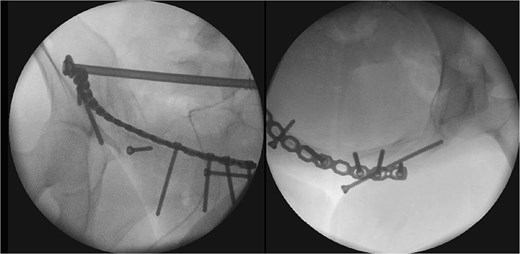

After one week of monitoring in the ICU, where she remained stable without need for ventilatory support, the patient was transferred to the ward. She then underwent the first surgical stage in supine position. Anterior pelvic fixation (Fig. 3a) was performed via a Pfannenstiel anterior approach combined with the first window of the right ilioinguinal approach, using a 3.5-mm reconstruction plate on the right anterior column crossing the pubic symphysis and a 3.5-mm retrograde screw in the left anterior column, inserted through the same Pfannenstiel access. During the same procedure, a 7.3-mm trans-sacral screw was placed in S1 on the right to stabilize the sacral fracture (Fig. 4). The surgery lasted ⁓3 h, and the patient was transferred to the semi-intensive care unit for postoperative monitoring.

The second surgical stage was performed under general anesthesia two weeks later, delayed by one week of hemodynamic monitoring and subsequent unavailability of surgical materials. In supine position, the left sacroiliac joint was fixed with two 7.3-mm cannulated screws, and a seroma in the Pfannenstiel approach was drained. Subsequently, with the patient repositioned in prone position (Fig. 3b), lumbopelvic fixation from L4-L5-S1 to the posterior ilium (EIPS) was performed using rods and pedicle screws (Fig. 5). This procedure lasted ⁓3 h. At this point, ˃3 weeks post-trauma, anatomical reduction was significantly hindered by early consolidation and fibrosis at the fracture sites, requiring extensive maneuvers. The patient was transferred to the ICU, extubated without complications the following day, and returned to the ward after two days, receiving hospital discharge thereafter.

The two-stage approach addressed initial severity (Fig. 3), using a Pfannenstiel and ilioinguinal approach for anterior fixation and an S1 trans-sacral screw for sacral stability [10, 11], followed by lumbopelvic fixation for posterior stability [12]. A 3-week delay, partly due to material unavailability, caused fibrosis, complicating reduction [13]. Seroma drainage in the second stage mitigated infection risks from the Pfannenstiel approach. ICU monitoring reflected management complexity despite stability [14]. Follow-ups over 18 months demonstrated functional recovery, quality-of-life gains, and psychological stability by 6 months, sustained to 18 months (Table 2, Fig. 7), despite early anxiety; this contrasts with studies linking severe psychological distress to poorer outcomes in Tile C fractures, suggesting early intervention mitigated these risks [5]. The Majeed score’s specificity, despite lacking a Portuguese version, and SF-12 supported outcomes analysis [15]. Pain assessment via the Numeric Pain Scale (NPS) revealed persistent lumbar pain radiating to right lower limb until the 4th week (NPS 4), resolving significantly by 3 months (NPS 1) and absent thereafter (Table 2, Fig. 7), consistent with rehabilitation progress and lumbopelvic fixation stability. This case underscores surgical timing challenges, the impact of delayed fixation, and multidisciplinary care’s value.